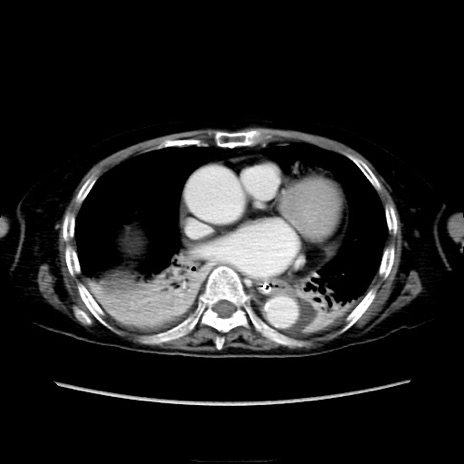

症例40(横断像)

【症例】90歳代女性

【主訴】腹痛・嘔吐

【現病歴】 食欲低下、嘔吐があり昨日他院受診。肺炎と診断され入院となる。入院後より腹部全体に圧痛あり。胃管留置され経過みていたが、症状持続するため、

当院転院となる。

【既往歴】胸椎圧迫骨折、胆石症

【身体所見】腹部:中央に激痛あり、圧痛あり、反跳痛不明

【データ】WBC 17100、CRP 18.82

他院CT

横断像